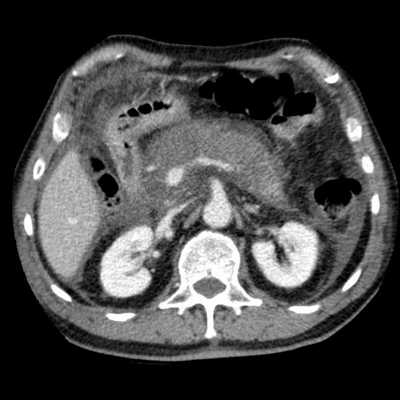

Острый панкреатит — фото КТ. Деструктивный панкреатит с вовлечением головки поджелудочной железы. Головка поджелудочной железы увеличена, вокруг железы определяется воспаление и экссудация.